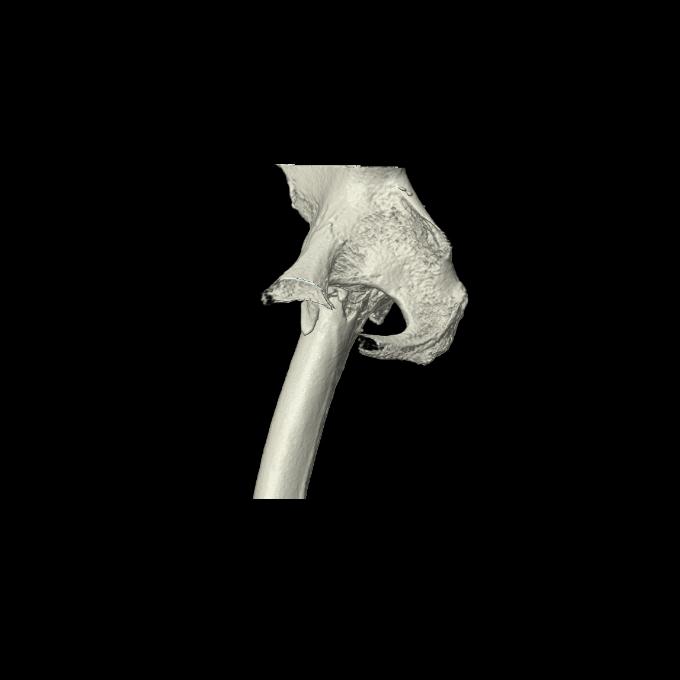

91569 3/25 両股正面とラウエン 70歳女性 人工骨頭+バンクーバー